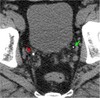

What are the red and green arrows poining to?

Green: Stone Red: Phleboliths